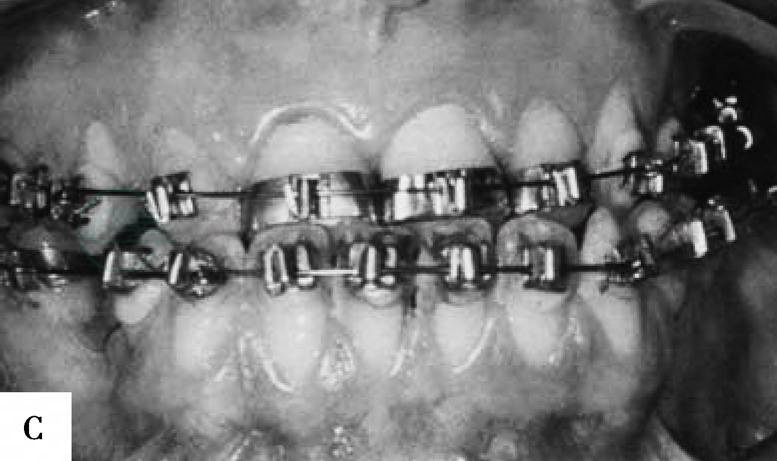

完成截骨并去除部分骨质后,将下颌的近心骨段和远心骨段进入到预制的板中并行颌间结扎固定。如果垂直截骨部位的软组织阻碍下颌远心骨段的后退可予部分切除,切除的软组织的宽度应小于下颌远心骨段后退的距离使骨组织后退后软组织能保持接触,利于术后缝合此处软组织伤口。可于下颌骨下缘处行骨间钢丝结扎固定,如果采用坚固固定方法可以用直的四孔接骨板配合以单皮质螺钉进行固定,需在下颌管上、下方各固定一个接骨板。坚固固定后可以将骨间结扎的钢丝去除,在缝合软组织切口前应检查骨段间稳定性和骨段位置。冲洗术野后用可吸收缝线缝合关闭软组织伤口。如果应用颌间固定方法进行固定,其术后应保持6~8周(图2)。

图2 下颌前突畸形患者,采用下颌体部台阶状截骨术进行矫正。A-D,患者术前面像和颌骨X线片。